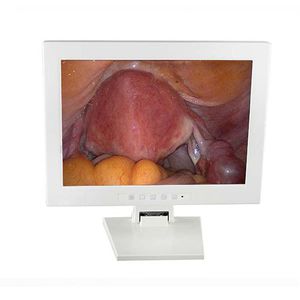

... UE视频设备兼容。 它提供实时的高清图像,在程序中得到支持。 兼容性 与UE视频设备兼容 与UE手推车兼容 检查用的大画面 连接方便 一条电缆直接与设备连接 无需连接小型显示器 2种颜色 黑色带设备 白色带喉罩 技术规格 尺寸 8英寸,比例4:3 内存 32G 分辨率 1024*768 px 工作时间 >3h 语言 中文、英文 重量 约740克 ...